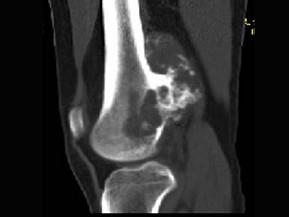

问题 女,20岁,右大腿远端疼痛2年,伴有肿块,请结合所提供图像,选择最佳答案 ( )

选项 A、纤维肉瘤 B、骨巨细胞瘤 C、软骨肉瘤 D、骨肉瘤 E、软骨黏液纤维瘤

答案 C